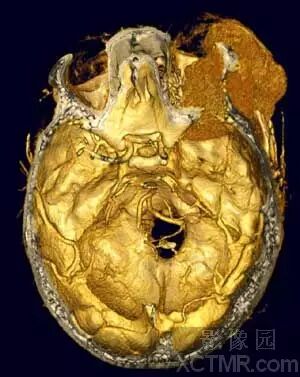

VR作为MS-CTA的主要后处理技术在血管系统特别是对动脉血管系统病变要以清晰、确切地显示大范围复杂血管的完整形态、走行和病变,图像立体感强,能以多角度直观地显示病变与血管、血管之间以及血管与周围其它器官之间的三维空间解剖关系,其诊断价值已经被临床医生认可。对大动脉血管病变如:动脉瘤、动静脉畸形、狭窄、梗塞、闭塞、夹层和血管壁的钙化等的诊断已经基本取代了DSA检查。对脑动脉瘤的诊断国、内外有关研究报告证实3D-CTA具有很高的准确性、敏感性和特异性,可以确切地检出瘤体直径<3mm的脑动脉瘤。作为一种快速和非创伤性检查手段,可以准确地显示瘤体的位置、形态和大小,评价瘤颈部与瘤体、载瘤动脉和周围血管之间的空间关系,模拟手术入路为选择适当的手术治疗方案提供直观、可靠的依据,可以作为脑动脉瘤的首选影像学诊断方法。近年来,有许多文献报道主张用3D-CTA取代或部分取代DSA诊断脑动脉瘤。

其图像后处理技术要点:

a)准确选择预设CT值的上下限,过高或过底均会影像病变显示的清晰度和真实性。但是,适当提高下限值可以鉴别后交通动脉是动脉瘤还是漏斗样扩张,逐渐改变域值后,动脉瘤仍保持圆顶,而漏斗样扩张则变成锥形;

b)用Clipping或Cutting等工具除去下矢状窦、直窦和大脑大静脉以及颅骨等影像的干扰;

c)从前后、后前、左右侧位和头侧和脚侧仔细观察血管形态查找动脉瘤;

d)适当调整伪彩色和遮盖光线的强度,以使图像更清晰、色彩更逼真;e)在疑有直径<2.0mm的动脉瘤时需要借助Fly-around技术辅助判定;

f)多角度旋转图像习可能清晰、完整地显示瘤颈部与瘤体、载瘤动脉和周围血管之间的三维空间关系;

g)对于后交通动脉瘤,也可行3D-MRA检查会更好地显露动脉瘤的全貌,而无颅底骨的干扰。